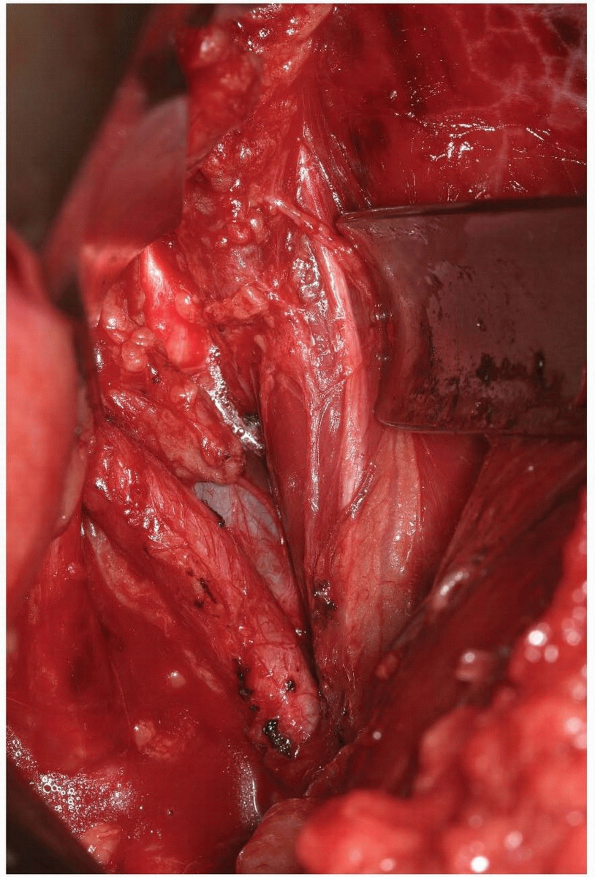

A rongeur or high-speed burr is then used

portion of the inferior lamina (Fig. 14-21). This will allow release of the insertion of the ligamentum flavum from the superior lamina of the caudal vertebra (Fig. 14-22). Immediately underneath this ligament is the epidural fat, thecal sac, and exiting nerve roots (Fig. 14-23).

After sufficient bone and ligamentum flavum have been removed the exiting nerve root should be visualized (Fig. 14-23).